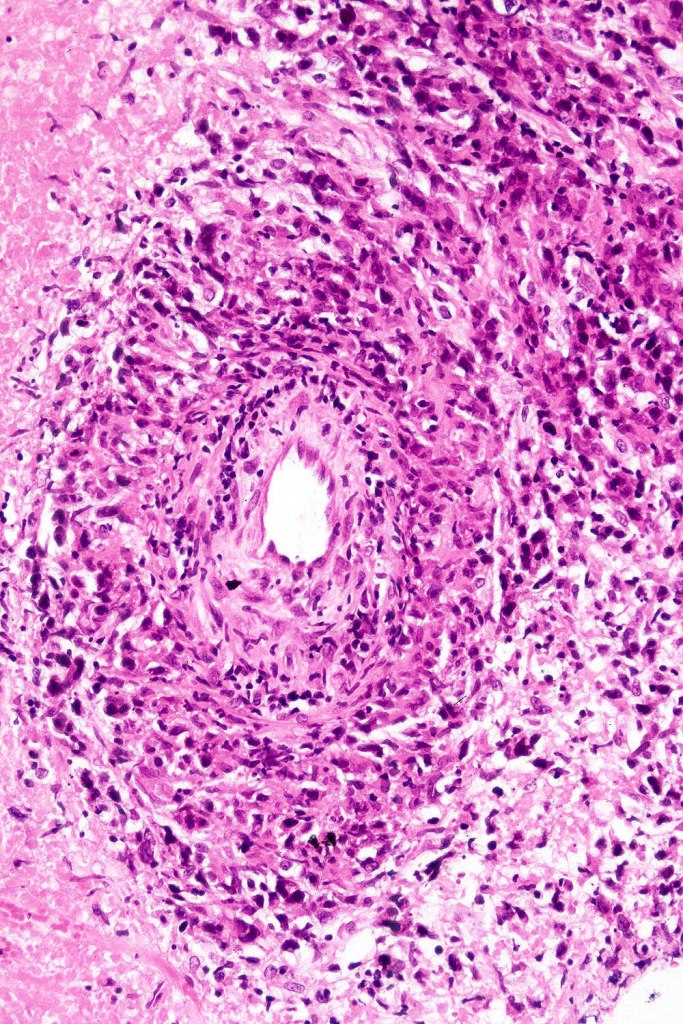

•Angiotropism, angiodestruction, thrombi & coagulative necrosis